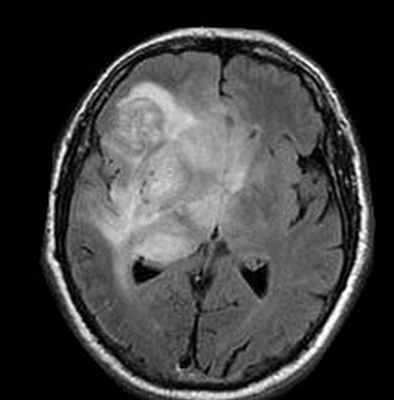

МРТ головного мозга. Глиобластома. Рост по типу «бабочки» (стрелки). Аксиальные Т2-зависимая МРТ, Т1- зависимая МРТ и Т1-зависимая МРТ с контрастированием.